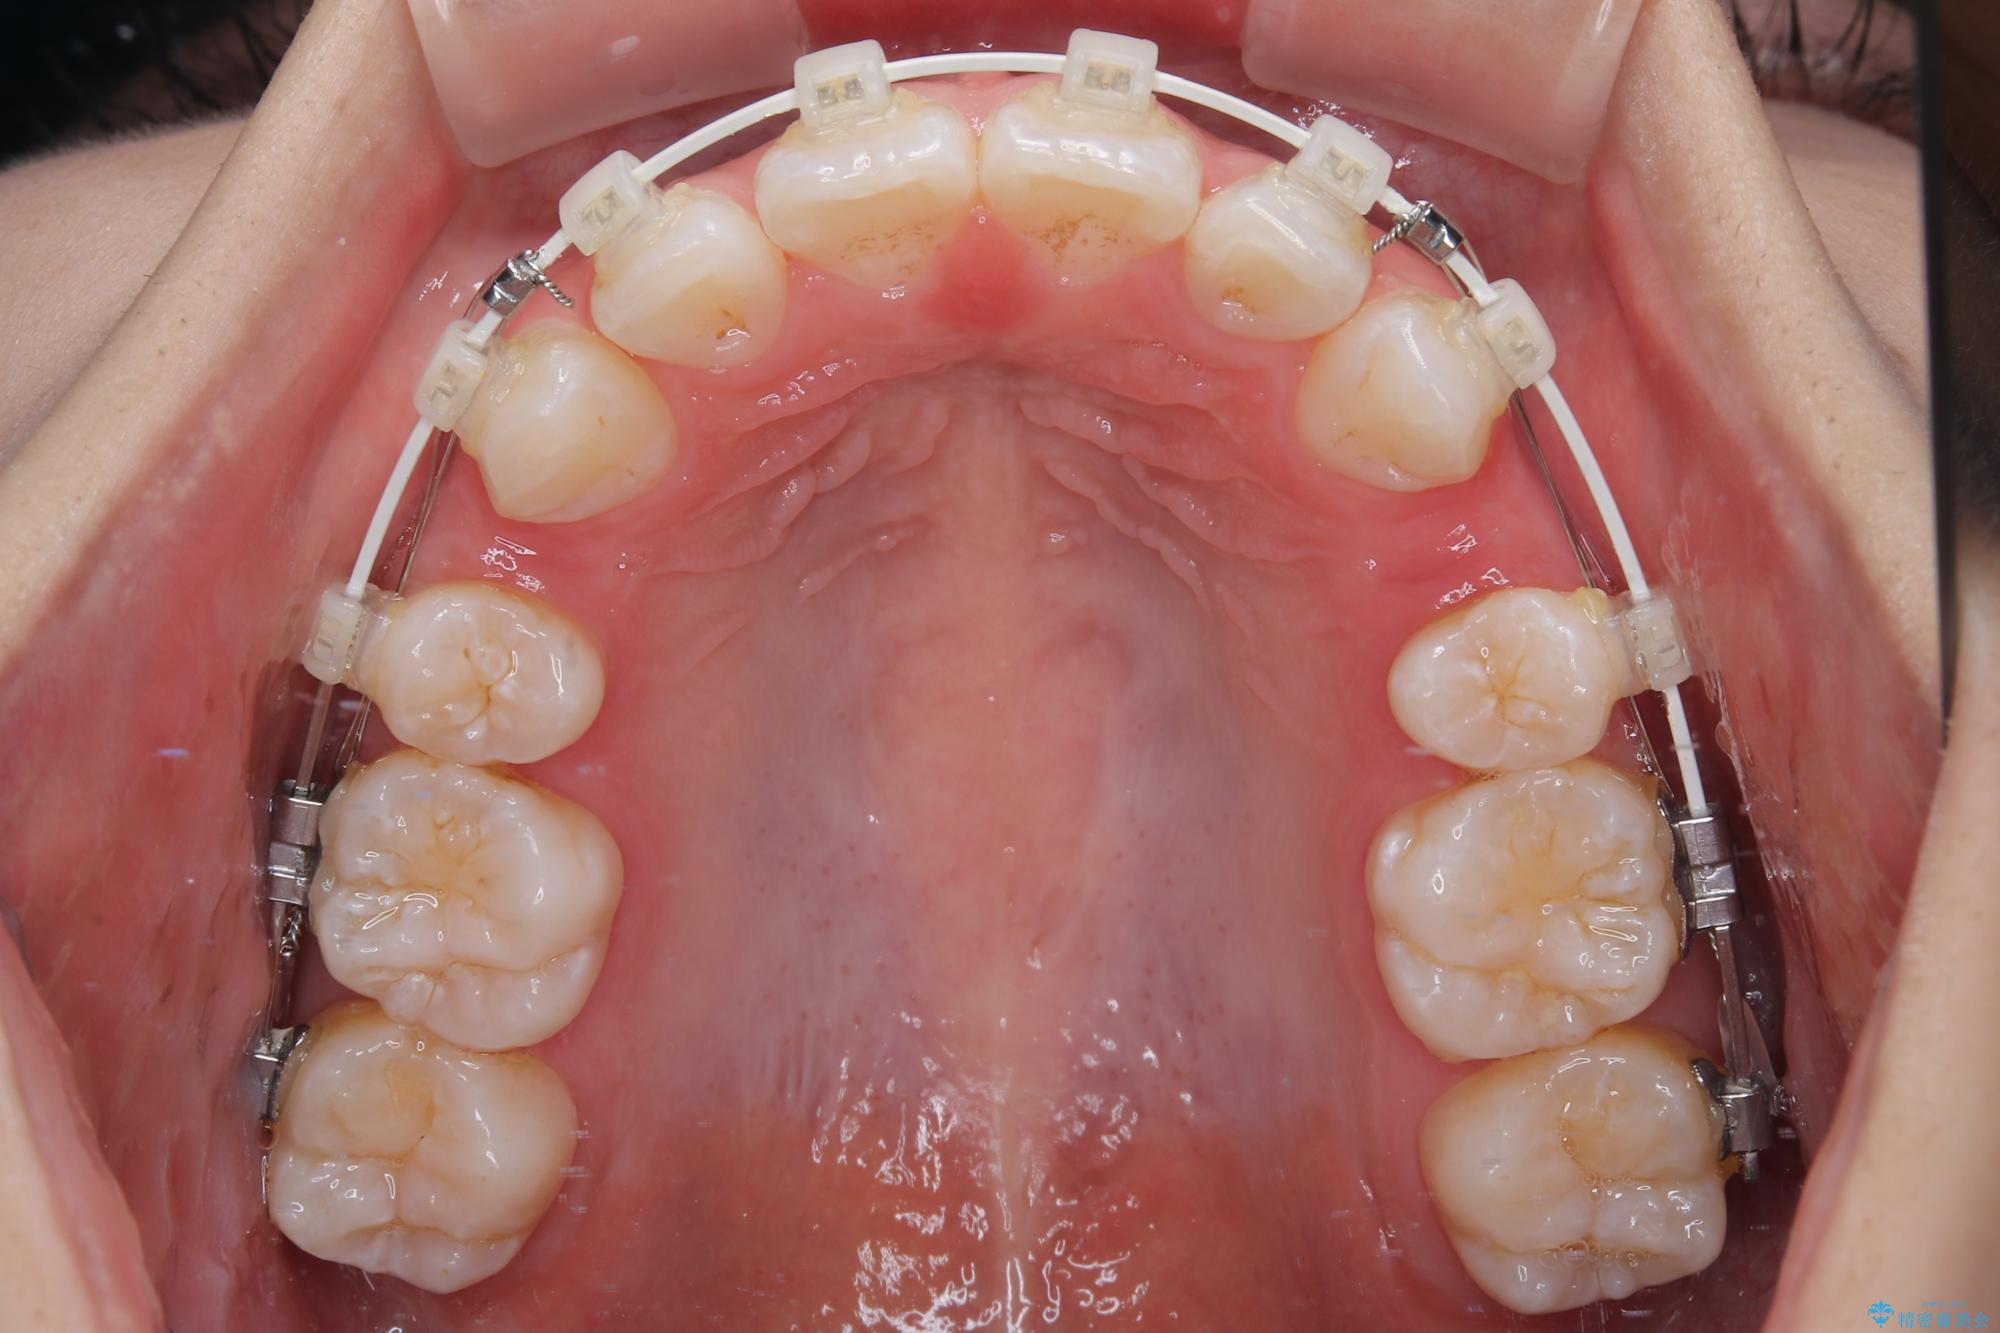

- 矯正装置

- 審美装置

- 口を閉じたときに飛び出してしまう上顎前歯を気にして来院された患者様です。

下顎はデコボコが気になっていたため、上下左右第一小臼歯4本を抜去して、ワイヤー装置にて口元の突出感を改善するよう矯正治療を行うこととしました。